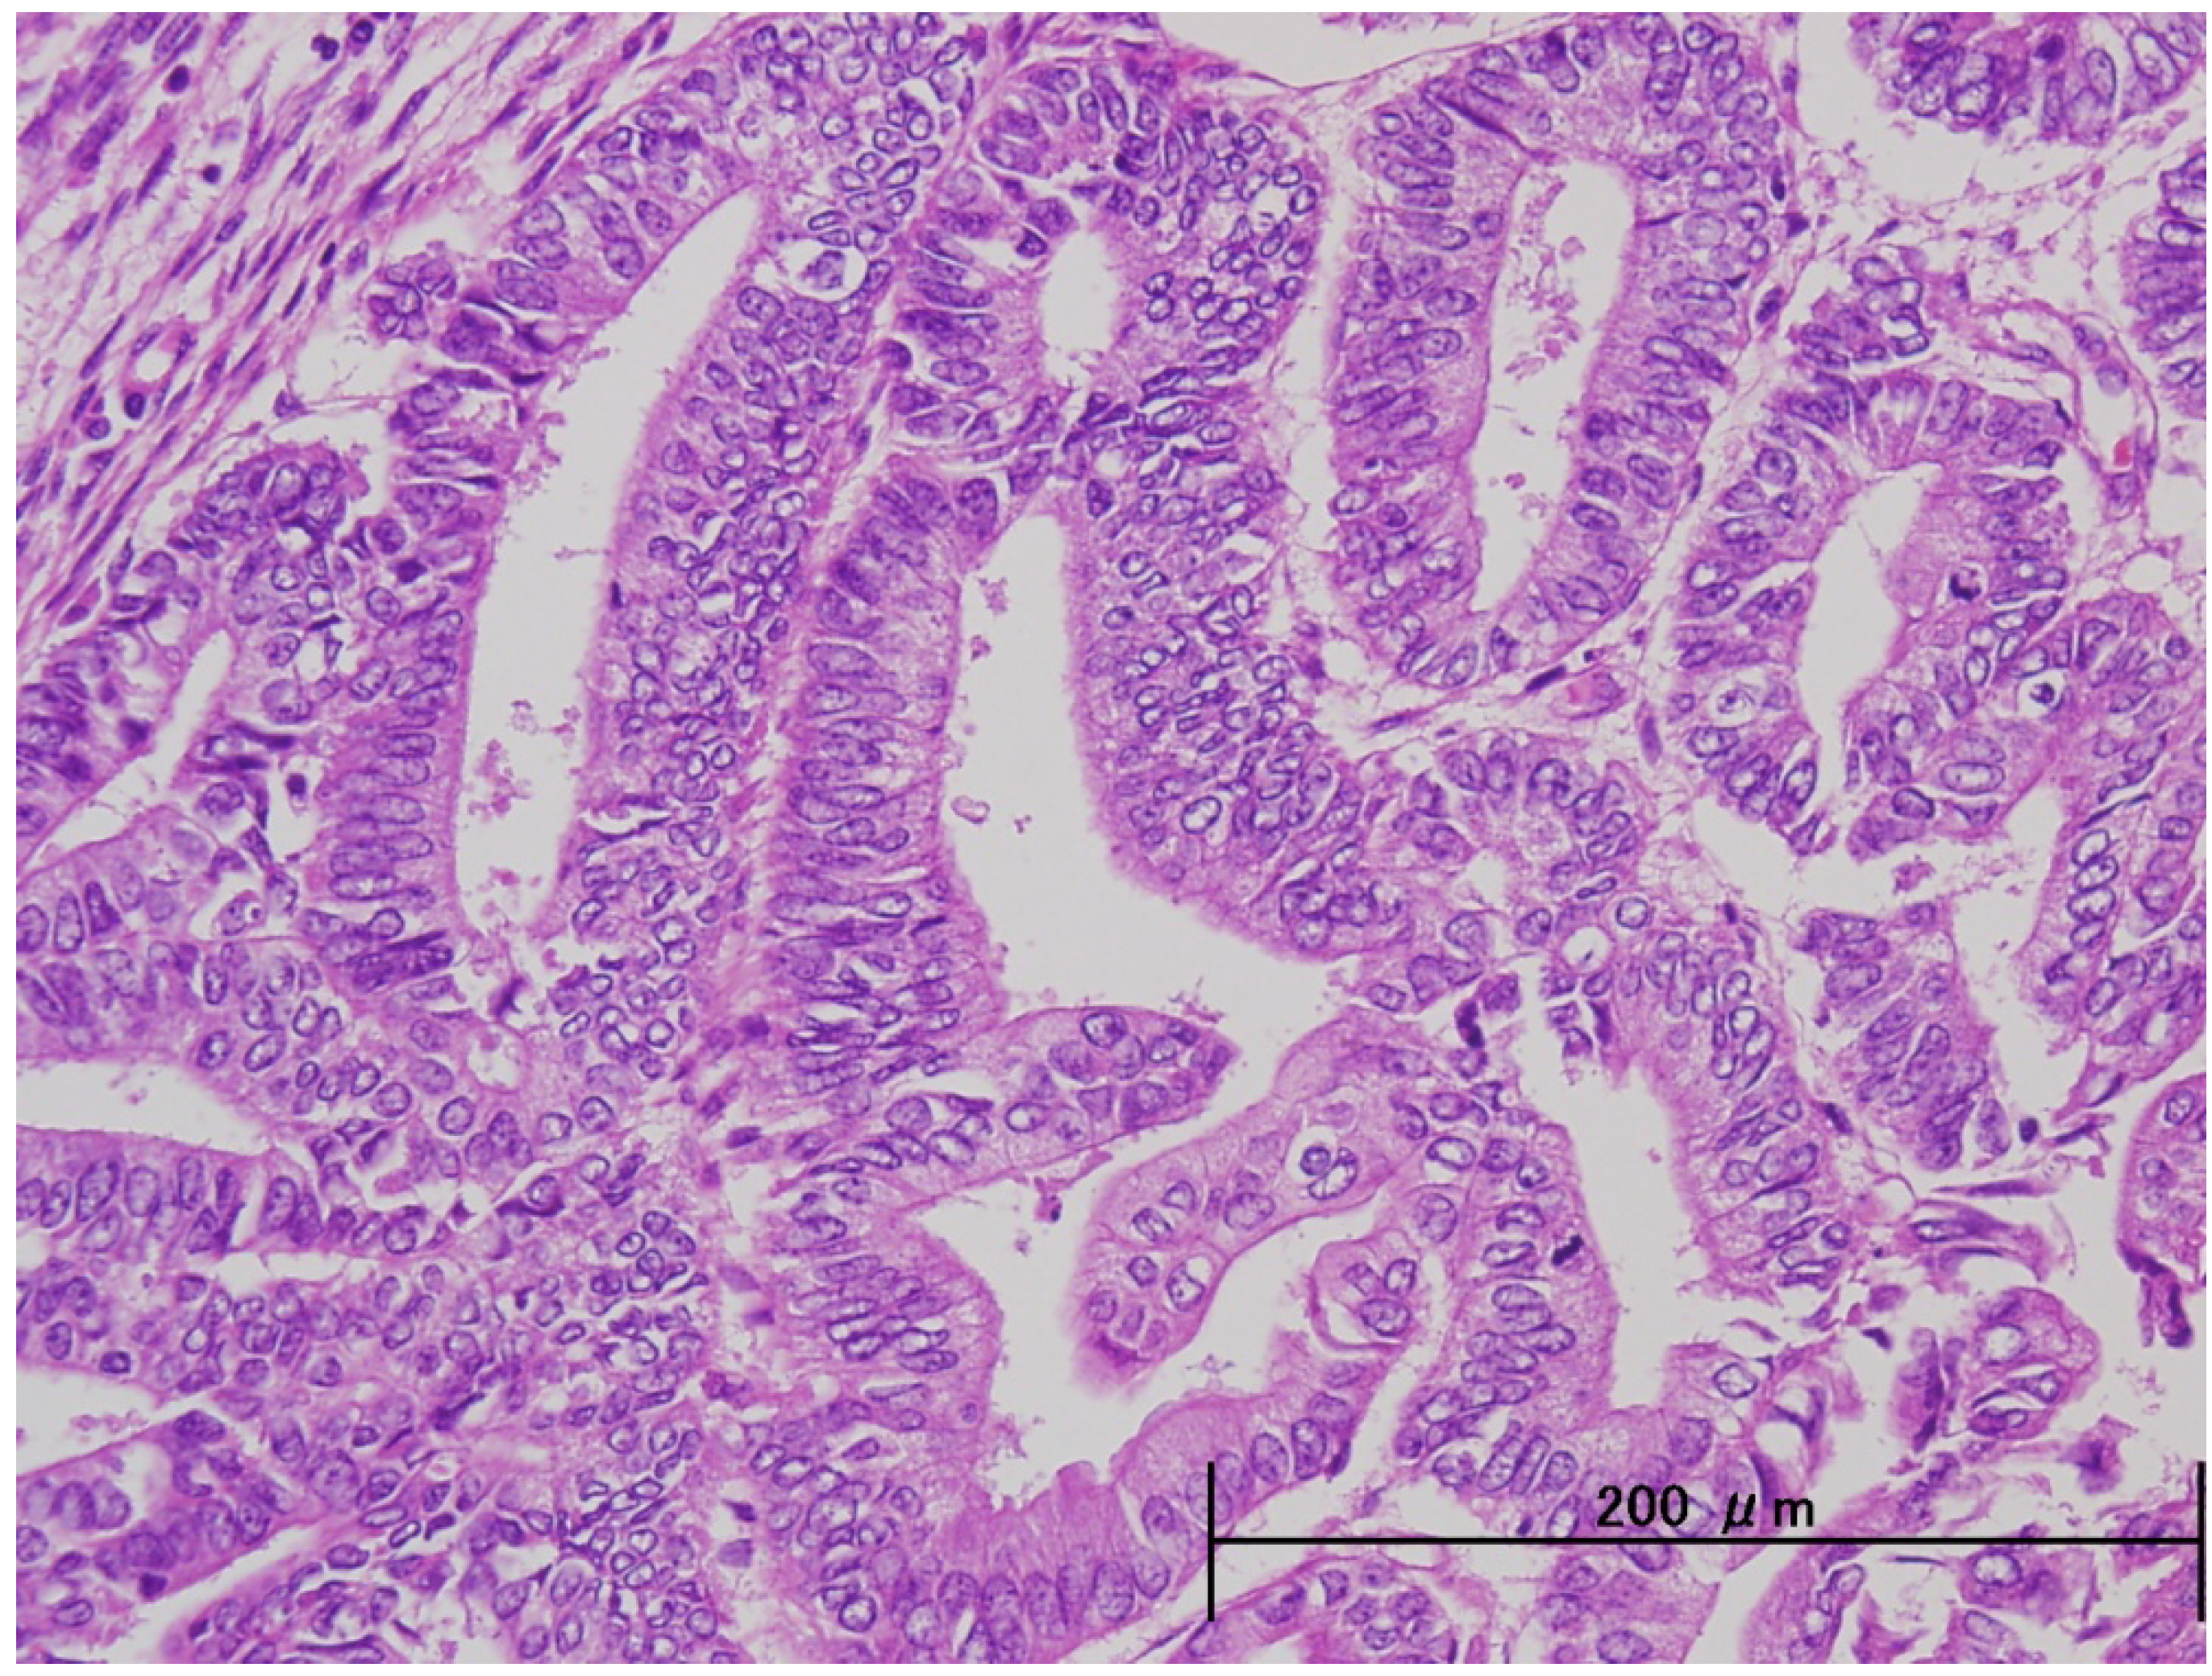

3. Pathological and Molecular Features of ESC